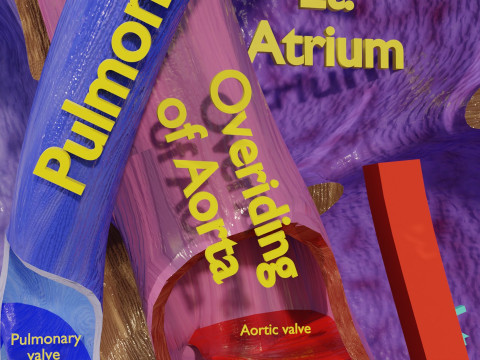

The model meshes include adult circulation versus circulation in Tetralogy of Fallot (TAF), arrow labels and text labels. The blood flow in a patient with Tetralogy of Fallot is outlined in this model. To contrast it to normal blood circulation a separate model of normal circulation is included. The Tetralogy of Fallot (OVER RIDING OF AORTA, PUL STENOSIS, VENTRICULAR SEPTAL DEFECT, RIGHT VENTRICULAR HYPERTROPHY), fossa, ligament teres , venosus, and arteriosus are duly depicted with proper labelling and blood flow directional arrows. Excellent model for teaching, demonstration and knowlegde of human body. The models include both procedural and image textures blend files separately. The texture file include diffuse, roughness and normal png and jpeg based on non overlapping UV maps.